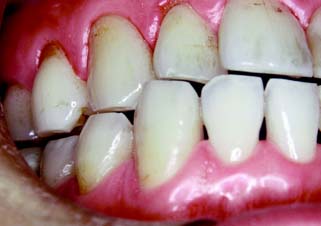

Wear has been observed on the functional surfaces of natural teeth that oppose porcelain restorations. This also applies to teeth opposed by metal-ceramic restorations, especially the mandibular incisors, which can exhibit significant wear over time (see Fig. 19-1).